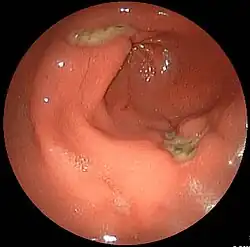

Panendoskopia umożliwia obejrzenie w czasie jednego badania kilku części przewodu pokarmowego:

- przełyku (ezofagoskopia)

- żołądka (gastroskopia)

- dwunastnicy (duodenoskopia).

Niektóre ze schorzeń, których wykrywanie stało się możliwe dzięki zastosowaniu panendoskopii:

- choroba wrzodowa żołądka i dwunastnicy

- zapalenie błony śluzowej żołądka, także wywoływane przez Helicobacter pylori